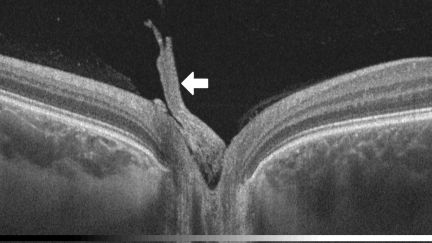

Bergmeister papillae can be observed with ophthalmoscopy and fundus photography (Figure 3), but they are more likely to be identified through optical coherence tomography (OCT) (Figure 1).[6][7][8] Visualization reveals a cluster of veil-like glial or fibroglial tissue emerging anteriorly, centrally, and nasally from the optic nerve head.[9][10][11] Presence of papillae can influence the size of the optic nerve head cup.[4] Bergmeister papillae can be unilateral or bilateral.[7]